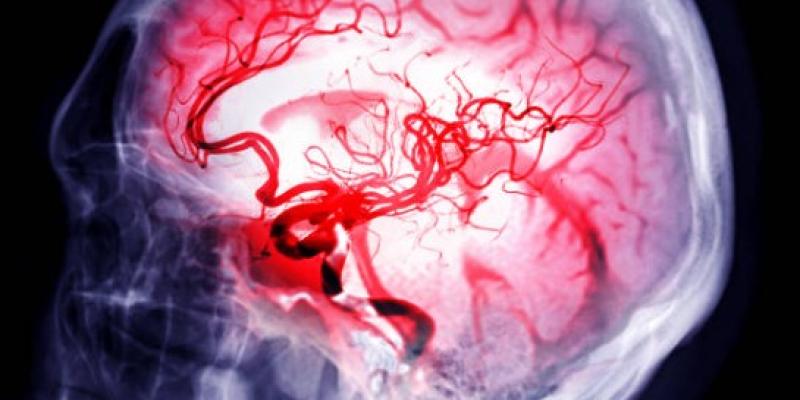

El ictus es una de las enfermedades más peligrosas para nuestro cerebro, ya que puede llegar a causar importantes lesiones en el él, que en muchos casos pueden llegar a superarse, pero que en muchos otros no. A esto se le suma además, que haber pasado por uno incrementa el riesgo de forma significativa de mortalidad, así como de otras situaciones como generar una discapacidad u otras patologías.

Esta eficacia se debe principalmente a la capacidad neuro protectora con el que actúa el medicamento y que llega a conseguir la respuesta inflamatoria que suele darse tras sufrir un ictus isquémico. Al lograr controlar esta inflamación, se reducen de forma considerable los riesgos de sufrir lesiones más graves o incluso de fallecimiento. En los testados que se hicieron en animales, este nuevo fármaco también demostró ser capaz de proteger el tejido cerebral.

Actualmente existen otros tratamiento para recuperar las lesiones cerebrales que quedan tras sufrir un ictus, sin embargo, estos hallazgos abren la puerta a una forma más eficaz de tratar las consecuencias de sufrir este accidente cardiovascular en el que se deja de bombear sangre al cerebro poniéndolo en una situación de importante peligro. A pesar de los buenos resultados, sus investigadores son cautos y consideran que es necesario realizar estudios mayores para terminar de sacar conclusiones.